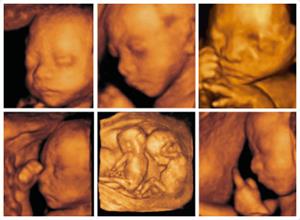

一般做大排畸是22—28周,安庆博爱专家指出孕妇在孕22到28周的时候做四维彩超比较好,这是因为这一阶段胎儿结构已经形成,胎儿的大小及羊水适中, 胎儿在宫内的活动空间较大,胎儿骨骼回声影响比较小,图像清晰,因此这个时期是进行胎儿畸形检测比较理想的时期,检查可排除大部分的畸形。

做四维彩超除了排查畸形以外,四维彩超可以清楚的看到宝宝在妈妈肚子里的实时动态活动图像,从而可以把宫内四维彩超宝宝的动态刻录成dvd,作为宝宝的0岁写真。